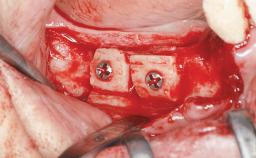

Autologous Block Graft and Guided Bone Regeneration (GBR) for Horizontal Ridge Augmentation in the Posterior Mandible

An 18-year-old man was referred for implant therapy in the posterior mandible to the Department of Oral Surgery and Stomatology (University of Bern, Switzerland). He was healthy and did not smoke. Tooth 35 was congenitally missing, involving a single-tooth edentulous space that offered an adequate mesiodistal dimension for implant placement but exhibited a typical pattern of buccal flattening. A panoramic radiograph was obtained, which revealed a sufficient vertical bone height above the mandibular canal and a normal bone structure in the edentulous area.

Bone Augmentation Horizontal|Staged

Augmentation Materials Autogenous chips|Autogenous block(s)|Xenogenous|Membrane

Bone Volume Deficient horizontally, requiring prior grafting